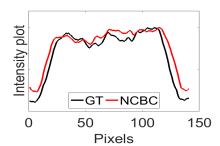

The calculated correlation coefficient (), SNR, as well as CNR values for all tested methods in the synthetic phantom experiment are shown in Table II. As seen in Table II, the proposed NCBC method achieved the highest , CNR as well as SNR values when compared to that of other tested methods. Visual results from the bias-corrected DW-MR synthetic phantom data produced using different tested methods is shown in Fig. 2(c-i). It can be observed that the MCBC, LEMS, and proposed NCBC method were able to achieve the best level of bias correction when compared to the other tested methods. This is particularly apparent in the peripheral zone (PZ) of the prostate gland as highlighted using red ROIs in Fig. 2(a-i), where intensity inhomogeneities are still present to a significant degree in the bias-corrected phantom data produced using the LS, SCIC, SGD and BCFCM methods, while strong inhomogeneity correction performance is achieved using MCBC, LEMS, and the proposed NCBC method. Furthermore, it can be observed that NCBC exhibited minimal intensity inhomogeneities when compared with MCBC and LEMS, particularly in the area that is highlighted using Red ROIs. To better represent the outperforming of proposed NCBC method in terms of bias correction using synthetic phantom, the data intensity profiles corresponding to the drawn blue line in Fig. 3(a) are shown in Fig. 3(b) for uncorrected data (red color plot) versus ground truth data (black color plot) and in Fig. 3(c-i) for corrected data using different tested methods (red color plots) versus ground truth data (black color plots). As the intensity profiles of Fig. 3(b-i) show, NCBC method was resulted in an intensity profile with the most flatness and less amount of variation compared to the intensity profiles of uncorrected image as well as reconstructed images using other tested methods as such confirms the better performance of proposed NCBC method in terms of bias field correction.